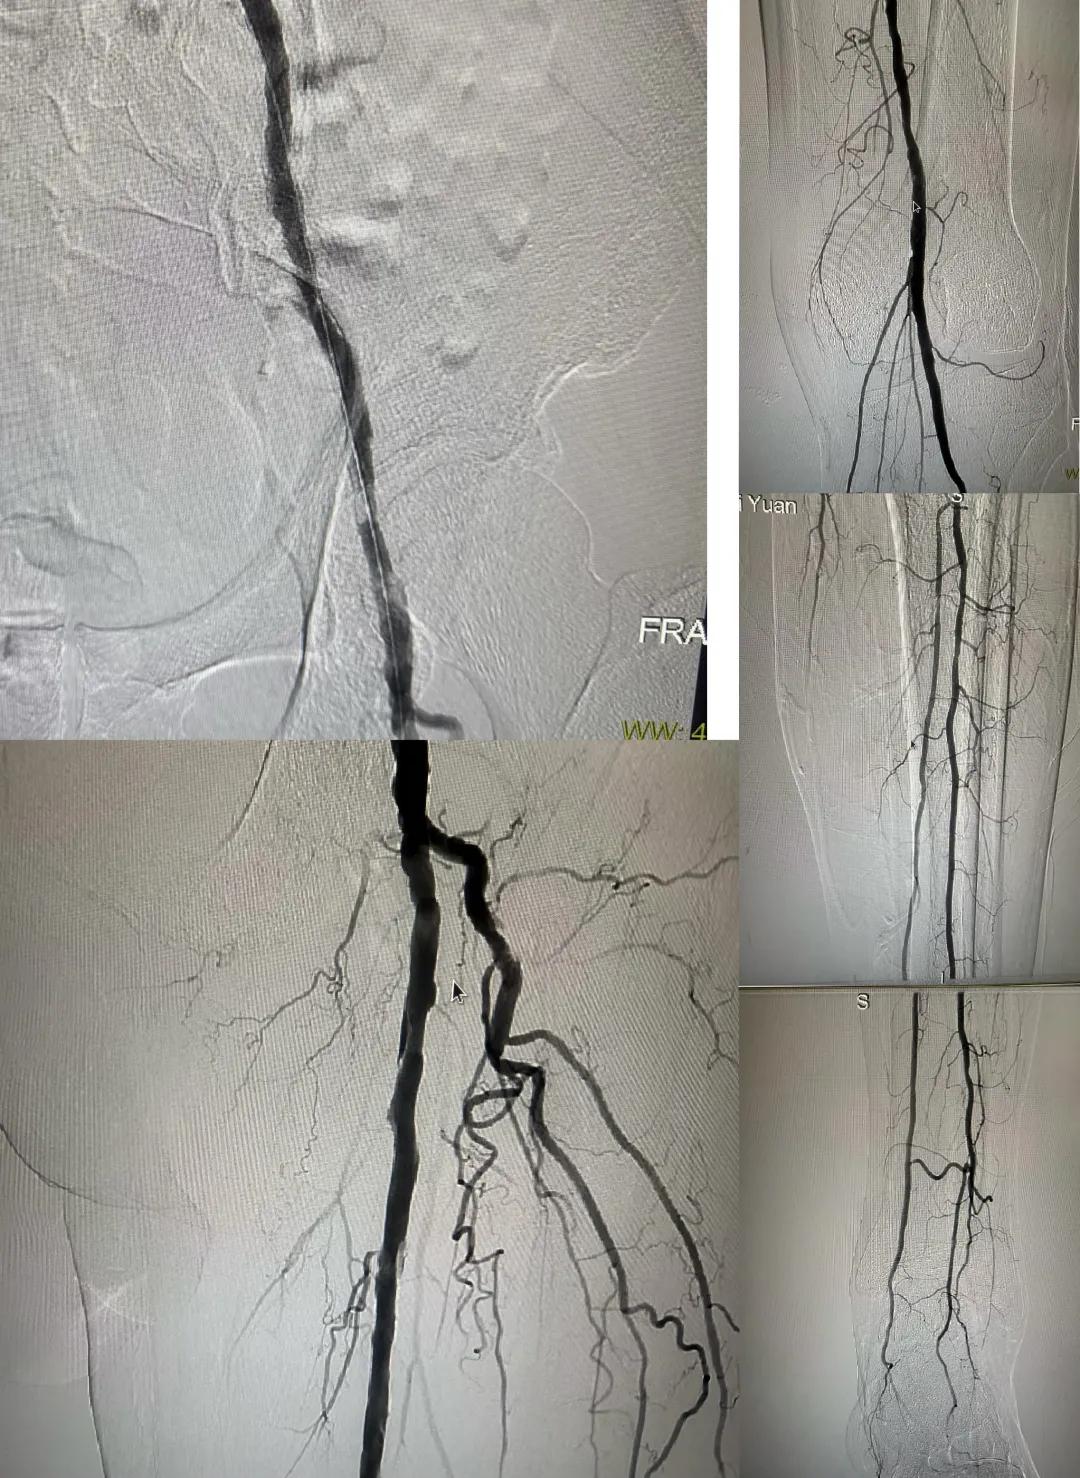

患者,男,73歲,約15天前出現(xiàn)左側(cè)腳面腫痛,間歇性跛行,左足第三足趾壞疽,遂來市中醫(yī)院就診,以“下肢動脈硬化閉塞、糖尿病足壞疽、”收住外二科,評估患者病情后需實(shí)施左下肢球囊擴(kuò)張成形術(shù)。術(shù)中造影見患者左側(cè)髂動脈、股淺動脈階段性重度狹窄。經(jīng)外周球囊擴(kuò)張術(shù)后,再次造影見股淺動脈、髂動脈血流通暢,膝下及足部血流速度較前改善。

術(shù)后已疏通血管成像